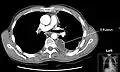

Chest computed tomography is more accurate for diagnosis and may be obtained to better characterize the presence, size, and characteristics of a pleural effusion. Lung ultrasound, nearly as accurate as CT and more accurate than chest X-ray, is increasingly being used at the point of care to diagnose pleural effusions, with the advantage that it is a safe, dynamic, and repeatable imaging modality.[9] To increase diagnostic accuracy of detection of pleural effusion sonographically, markers such as boomerang and VIP signs can be utilized.[10]

Massive pleural effusion, later proven to be hemothorax in a South Indian male.